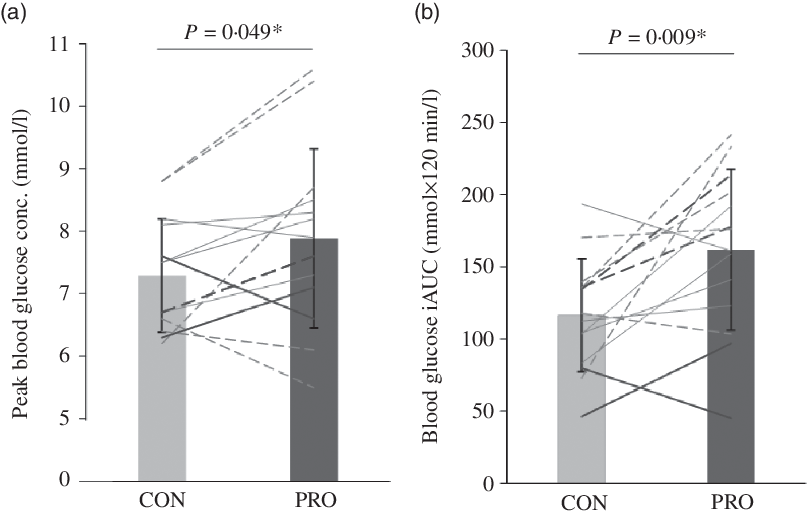

Blood glucose concentrations increased more rapidly in PRO than in CON, reaching a 7·5 % higher peak (7·9 (sd 1·4) v. 7·3 (sd 0·9) mmol/l, P = 0·049, d = 0·50, moderate effect; Fig. 3(a)) and then remaining higher than the CON trial until the final blood sample, such that there was a main effect of treatment (P = 0·037, F = 5·392) but no treatment × time interaction (P = 0·308, F = 1·241; Fig. 4). Accordingly, there was a 28·1 % mean increase in post-prandial blood glucose iAUC in the PRO condition (161·8 (sd 55·7) v. 116·3 (sd 39·2) mmol × 120 min/l (P = 0·009, d = 0·94; Fig. 3(b)). Time spent above the clinical threshold of 7·5 mmol/l blood glucose concentration was longer in the PRO trial for nine out of fourteen participants by an average of 8·2 (sd 13·4) min (15·9 (sd 17) v. 7·7 (sd 11·6) min, P = 0·039, d = 0·56, moderate effect). Although not significant (P = 0·206, d = 0·48, small effect), on average there was a 6·4 (sd 18·3) min delay in time to peak glucose with PRO (37·5 (sd 16·4) min) compared with CON (31·1 (sd 9·2) min).

Fig. 3. (a) Peak blood glucose concentration (conc.) and (b) incremental area under the blood glucose concentration curve (iAUC). Dashed lines denote female (n 7) and solid lines denote male (n 7) participants. Darker lines represent individuals with a BMI > 25 kg/m2 (n 4) and lighter lines denote those with a BMI < 25 kg/m2 (n 10). * Significant difference between control (CON) and protein (PRO) trials.